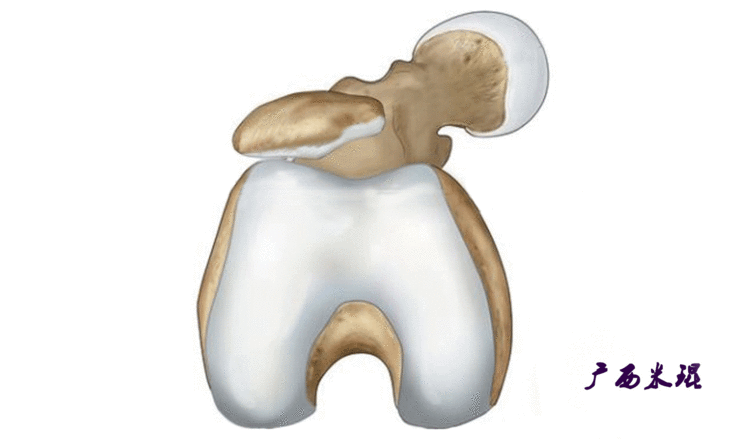

说到髌骨脱位,首先就要了解髌骨,髌骨是人体最大的籽骨,倒三角状位于膝关节前方,它的上缘与股四头肌腱相连,下缘通过髌韧带止于胫骨结节上,两侧为股四头肌扩张部,髌骨后方的凸面为光滑的关节面,与股骨下端内外髁之间的滑车凹面关节面形成关节。尽管股四头肌中的股直肌、股中间肌、股外侧肌的作用方向与髌韧带不在一条直线上,髌骨有向外突出的倾向,但因股内侧肌有向内上方牵拉作用力而使髌骨维持在正常位置。